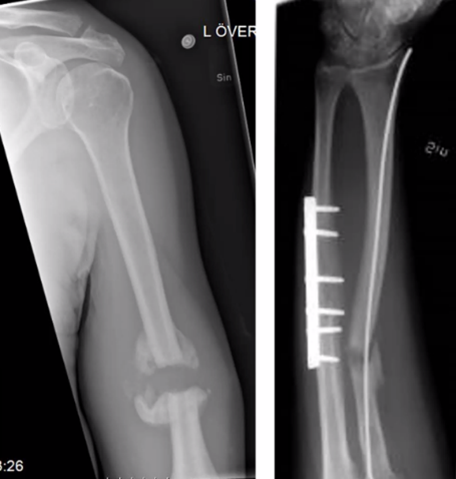

21

Q

23-årig kvinna påkörd av bil som cyklist. Vad göra?

Märghålan inte så stor så man mäter med DT och märghålan mäts till 6 mm (för litet (8-9 mm som minst)) därför platta om vi opererar men, vad kan vi göra också?

A

Tibiafrakturen ligger fint (odislocerad) så man kan gipsa i tre månader